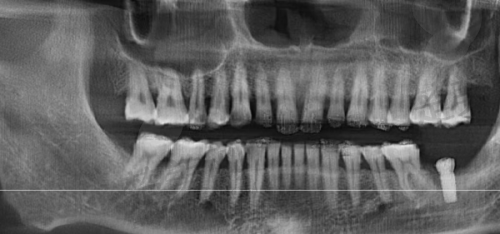

1. 空军军 医 大学第三附属医院(原第四军 医 大学口腔医院)这家医院可是国内口腔领域的具有影响力呢!它有独立的种植科,医生团队经验那叫一个丰富,特别擅长处理复杂的病例,像骨量不足、全口种植这些难题,对他们来说都不在话下。而且医院的设备特别精良,种植材料的选择也多种多样。不过呢,它也有个小缺点,就是预约周期比较长,大家要是想去这里种牙,可得提前做好规划。

比如说,有位患者牙槽骨骨量重度不足,特别多医院都觉得手术难度太大不愿意接手。后来来到了第四军医大口腔医院,医生们凭借丰富的经验和精良的技术,为他制定了详细的种植方案。手术非常成功,患者种上了一口好牙,修复了正常的咀嚼功能。